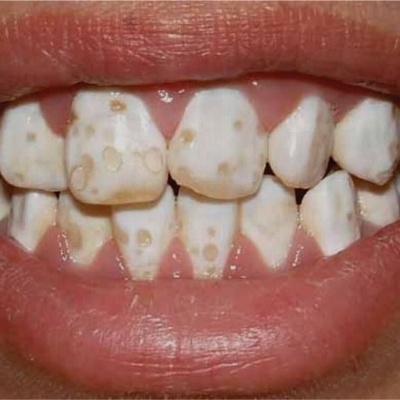

پیشگیری از کرم خوردگی دندان در کودکان

جلوگیری از سیاه شدن دندان کودکان با قطره آهن